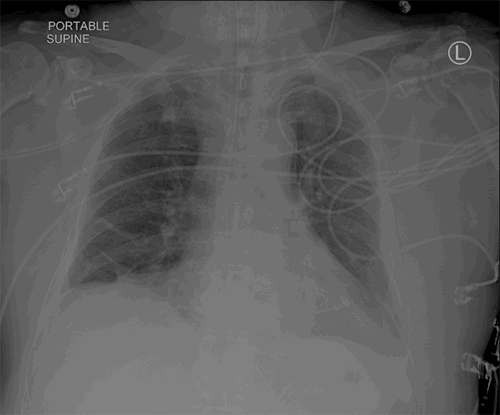

A 72-year-old man presented to the emergency department with shortness of breath, dyspnea on exertion, a hacking, productive cough, and left-sided chest pain. He had no history of trauma. He had a 50-pack/year smoking history and continued to smoke after being placed on home oxygen. His admitting chest radiograph revealed a small left pleural effusion and changes consistent with COPD (Figure 1). A previous chest radiograph was reviewed and revealed only changes of COPD and no evidence of left diaphragm eventration. He was hospitalized for nebulizer therapy, acute administration of intravenous steroids, and to rule out an acute coronary syndrome. During his admission, he began complaining of abdominal distension and constipation and continued to have a chronic cough. On physical examination, he was obese (BMI 33.7 kg/m2) with a pulse of 102 and labored breathing. Chest auscultation revealed diffuse rhonchi with diminished breath sounds at the left lung base. His abdomen was distended, tympanitic, and diffusely tender. There was ecchymosis along the left flank extending to the left lower quadrant, consistent with Grey Turner sign. Laboratory studies revealed a white blood cell count of 18,300/μL, and arterial blood gas showed a pH of 7.34, pCO2 of 42 mmHg, and pO2 of 60 mmHg on 5 L/min by nasal cannula. An electrocardiogram demonstrated sinus tachycardia but no ischemia. A plain film now revealed loops of bowel in the left hemithorax (Figure 2).

Figure 1. Plain radiography of the chest four days prior to hernia repair showing a small left pleural effusion